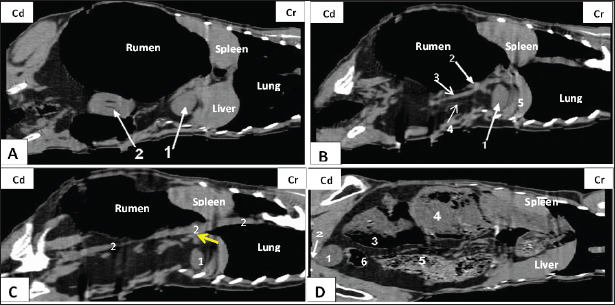

A dorsal-plane CT scan revealed the presence of the right renal vein, which extended from the right kidney toward the caudal vena cava (Fig. 4). Both transverse and dorsal plane CT scans revealed the presence of the right renal artery, which originates from the aorta and extends toward the right kidney (Figs. 2, 4). Following its entry into the renal hilus (Fig. 2), the structure underwent bifurcation into its dorsal and ventral branches. In the dorsal-plane CT scan, the right ureter was positioned dorsally adjacent to the caudal vena cava, extending toward the urinary bladder. The lumen was smaller in size compared with the renal vein (Fig. 4).

The egress of the left ureter from the left renal hilus was observed in the transverse CT image (Fig. 2). On transverse- and dorsal-plane CT scans (Figs. 3, 4), the urinary bladder may be identified at the sacrum level on the pelvic floor, located beneath the uterus and rectum. A dorsal-plane CT scan revealed the presence of the urethra exiting the urine bladder in a caudal direction (Fig. 4).

Fig. 3. Representative macrographic image of cross-sectional anatomy (Panel A) and computed tomography image (5-mm thickness) (Panel B) of the goat pelvis. Panel (A –B): 1- Sacrum; 2-Urinary bladder; 3- Rectum; 4-Uterus.

Fig. 4. Representative computed tomography image of the goat trunk in the dorsal plane. Panel (A): 1-Right kidney; 2-Left kidney. Panel (B): 1-Right kidney; 2-Right renal vein; 3-Caudal vena cava; 4-Right ureter; and 5- caudate lobe of the liver. Panel (C): 1-Right kidney; 2-Aorta. Panel (D): (1) urinary bladder; (2) urethra; (3) intra-ruminal gases; (4) rumen; (5) intestinal; (6) colon.